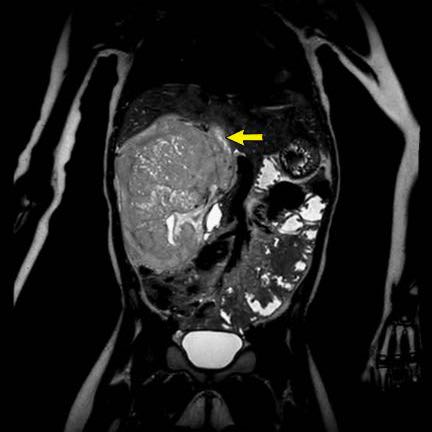

Ca lâm sàng 1

Hình ảnh chuỗi xung T2W mặt phẳng coronal cho thấy một khối u không đồng nhất ở thận trái với các thành phần nang nhỏ.

Khối u ngấm thuốc kém hơn so với phần nhu mô thận bình thường còn lại ở ngoại vi.

Các thành phần đặc của khối u cho thấy hạn chế khuếch tán rõ rệt (mũi tên).

Đây là u Wilms ở bé trai năm tuổi. Hóa trị tiền phẫu được thực hiện theo phác đồ Umbrella của SIOP-RTSG, sau đó tiến hành cắt thận.